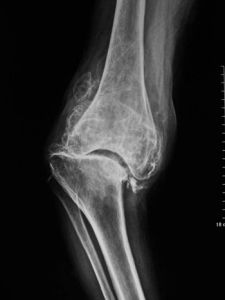

X線平片於早期並無明顯異常,約數年後方逐漸出現關節間隙狹窄,此表明關節軟骨已開始變薄。開始時,關節間隙在不負重時正常,承重後出現狹窄。病變後期,關節間隙有顯著狹窄,軟骨下可有顯微骨折征,而後出現骨質硬化,最後關節邊緣變尖,有骨贅形成負重處軟骨下可有骨性囊腔形成典型的骨關節病徵象。CT及MRI檢查可在早期發現關節軟骨及軟骨下骨質的異常改變。